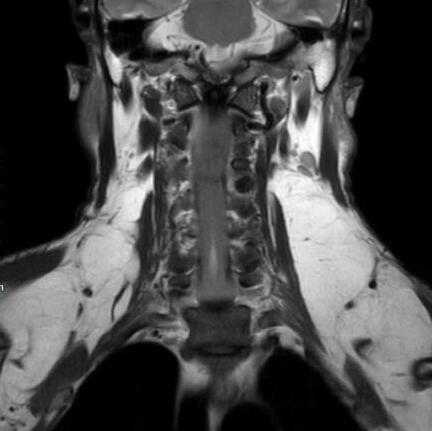

马德龙病的影像表现为颈项部等处脂肪组织蓄积增厚,可累及皮下或肌肉间隙,脂肪蓄积处没有包膜形成,蓄积脂肪内可有线状或网状纤维间隔,病变常常左右对称,颈部肌肉可受压、变细,蓄积脂肪组织内可有钙化或骨化。

刀某颈部MRI

李某颈部MRI